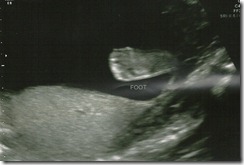

A girl is on her way…

A week and a half ago, we had our official gender-reveal ultrasound. This was a source of much debate in our house as we tried to decide whether to find out the sex at all. We did not know that Miles was a boy until he was born, and we never regretted not knowing, but for some reason I just wanted to know this time. And since the baby is currently kicking my bladder, I felt I had a say in the matter. Chris didn’t want to find out, but he was willing to go along  with whatever I decided (what a good man).

I think the real reason he didn’t want to find out was that he was worried that it would be a girl. For some reason Chris has it in his mind that a girl will be much harder to raise than a boy. And more expensive. I’ve been trying to convince him that that little girls do sometimes have more drama, attitude, and emotion than boys, but that doesn’t mean that she will be a terror just because she is a girl. He’s worried that she won’t want to wrestle or go hiking with him, but I think she will love anything that we raise her to love. And yes, she will probably be more expensive, but I don't know if there is anything I can do to change that.

I’m of course really excited to have a girl because I think all moms want a girl, but Chris is still coming around to the idea.  Oddly he’s the one that suggested that we buy new bedding for the nursery when she’s born, and I’m the one that planned on re-using what we already have (especially because it’s gender neutral). But if he insists on buying something new, I guess I can’t argue that.